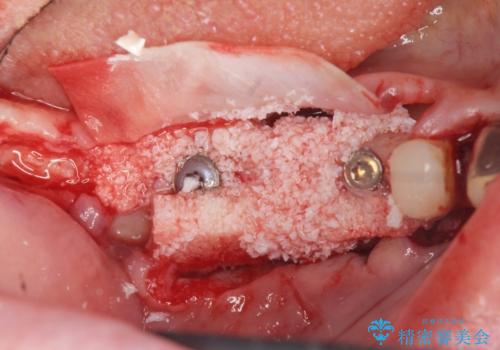

- インプラント治療を希望し数軒の医院で治療の相談をするも、骨の量が足りず治療が難しいと断られたのち当院にも相談にみえました。

長年の義歯の使用により骨の幅は非常に薄くインプラントを埋入するには大規模な骨の造成が必要な状態です。

また骨の問題だけでなく、完成後に歯ブラシがしやすいよう歯ぐきの移植も行いよりインプラント周囲の環境が安定するよう環境を整える治療計画を立てます。

- 110万円(インプラント×2 チタンカスタムアバットメント×2 フルジルコニアクラウン×3 骨増成 歯肉移植)費用は治療当時の料金となります

インプラントを埋入するには十分な骨の量が必要で、吸収して少なくなってしまった場合でも造成できる場合があります。